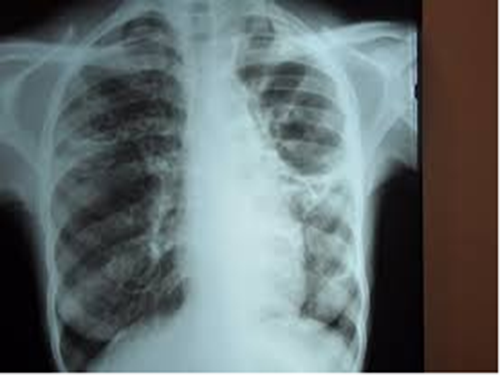

肺结核传染途径

有生活常识的人应该都知道有的疾病是具有传染性的,而有的疾病是没有传染性的,对于有...